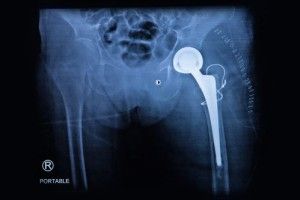

depuy-hip-lawsuitPatients have been using hip replacement surgery to restore their movement and to eliminate the pain from basic movements.

Hip replacement surgery has been around for at least 40 years, helping millions of patients suffering from painful arthritis, pelvic injury and to improve the overall quality of life for patients suffering from hip pain.

At this time there are approximately 450,000 patients that undergo hip replacement surgery each year, with many of them opting for metal on metal hip replacement models. Initially only plastic and ceramic models were available, but metal on metal hip replacement has been on the rise for the past several years.